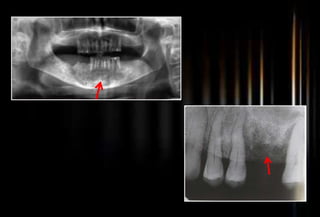

Conventional Radiographs(H.M.Worth-1969)

 Moth-eaten appearance

 Enlargement of medullary spaces

 Destruction and replacement

 Islands

 Sequestra, with evidence of a

trabecular pattern and

marrow spaces.

 A sheath of new bone

(involucrum) often is found,

separated from the sequestra

by a zone of radiolucency.